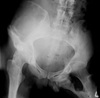

47

What is demonstrated in the right ilium?

Hemophiliac pseudotumor (geo. Lytic lesion)

48

What is occurring medial to the left hip?

Myositis ossificans